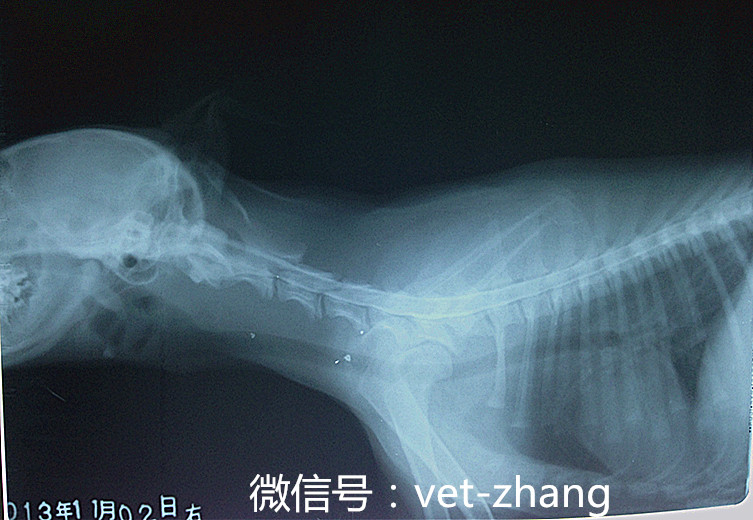

此图是一只大型犬,进针部位为L4 L5注射造影剂一分钟后拍摄的X光片